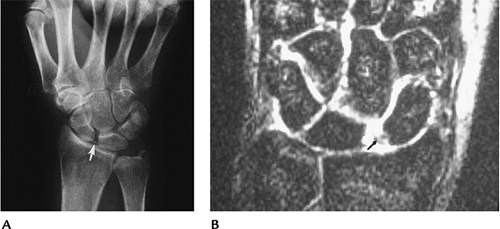

FIGURE 9-34 Scapholunate tear. (A) Clenched-fist view showing widening of the scapholunate joint (arrow). (B) Coronal T2-weighted image showing the ligament tear (arrow).